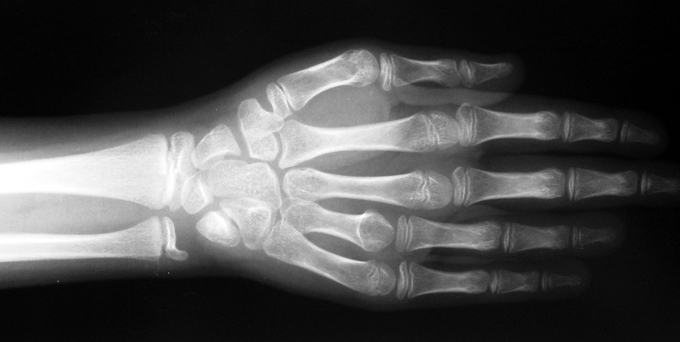

Finger (metacarpus) and toe (metatarsus) shortness can be seen congenitally as a single deformity or as a part of various syndromes; or after trauma or Freiberg disease (avascular necrosis). The frequency of congenital metacarpal or metatarsal shortness is less yhan 1/1000. It is seen 5 times more freqently in women and usually (72%) bilateral. Fourth finger is the most frequently involved. Although the cause of this problem is not known exactly, it is believed that the deformity is usually caused by early closure of the growth plate.

Surgical treatment may be required for metacarpal shortness because of cosmetic disturbance and fatigue in the dominant hand; and for metatarsal shortness because of cosmetic appearance, metatarsalgia, deformity due to dorsal shift of the short finger, pain and pressure ulcers due to plantar shift of the short finger, or difficulty in shoe wearing. Various techniques have been defined for the treatment of congenital metacarpal or metatarsal shortness. However, the most frequently used methods are acute lengthening with grafting, and distraction osteogenesis (callotasis). Callotasis method is preferred for lengthening more than 1 cm. In our department, we prefer distraction osteogenesis with unilateral or circular external fixator for lengthening of metacarpal and metatarsal bones.